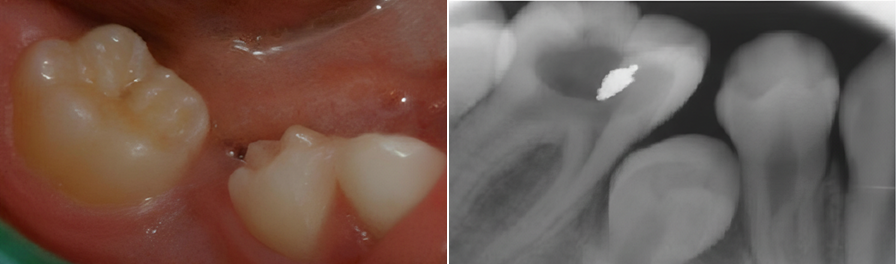

Süt dişlerinde oluşan çürükler zamanında tedavi edilmezse, enfeksiyon gelişebilir ve alttaki daimi dişleri etkileyebilir. Yukarıdaki görüntüler, erken dönemde müdahale edilmeyen diş çürüklerinin klinik ve radyografik görünümünü göstermektedir.